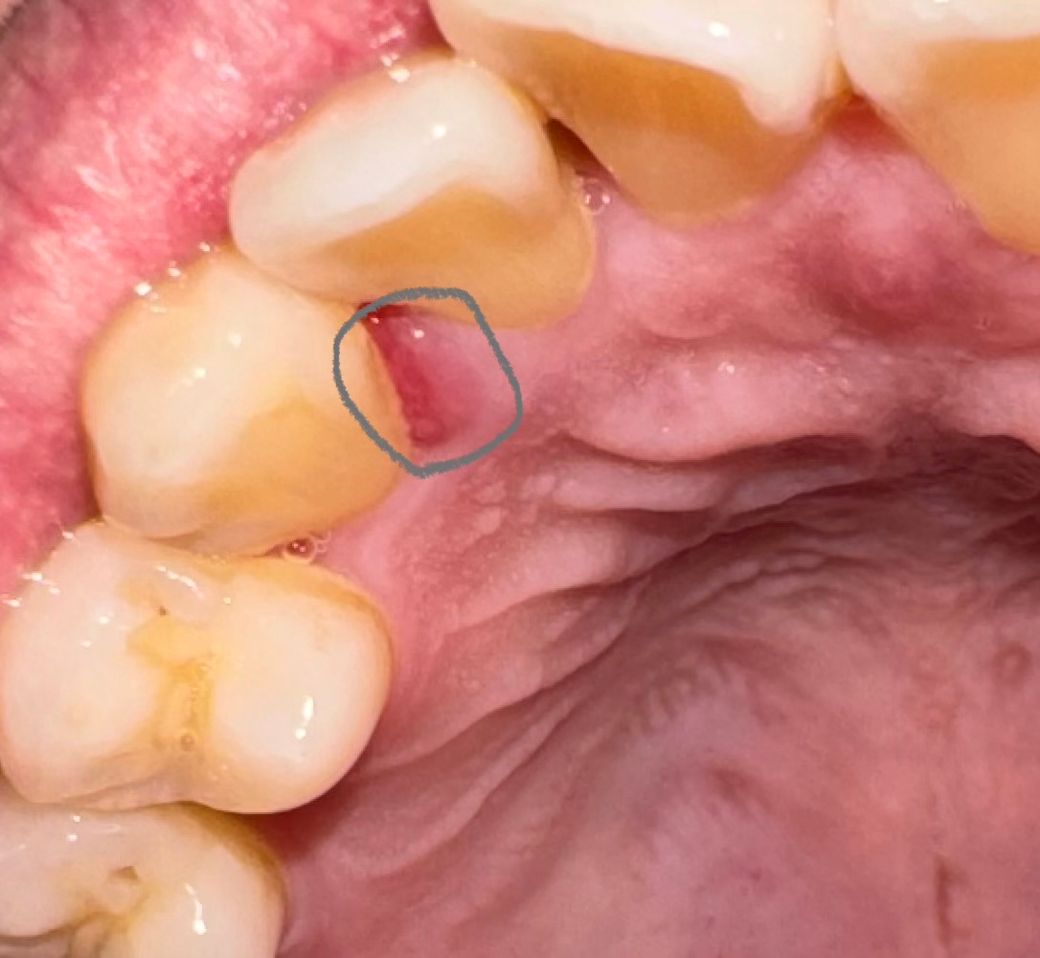

몇일전부터 양치하고 치간칫솔사용중에 피가 나서

따끔해서 그러려니햇다가 치아통증같은거는 없는데

저부분에 상처같은게 나서 괜히 신경쓰이는데

잇몸염증같은거일까요?

아니면 상처가 생겨서 부어서 그런걸까요?

치과검진은 한달전쯤에 검진 및 스케일링치료했습니다.

관리방법좀 알려주세요. 잇몸상처회복은 오래걸릴까요?

해당 부위는 치은염이 생긴 것으로 사료되며 가볍게 양치 및 구강위생관리를 통해 증상완화 가능하리라 봅니다. 다만 사진 상으로는 정확히 알 수 없으며 증상 지속시에는 추가적 처치 요할 수 있습니다. 너무 자극은 주지 마시고 조심스래 구강위생관리하시기를 바랍니다.